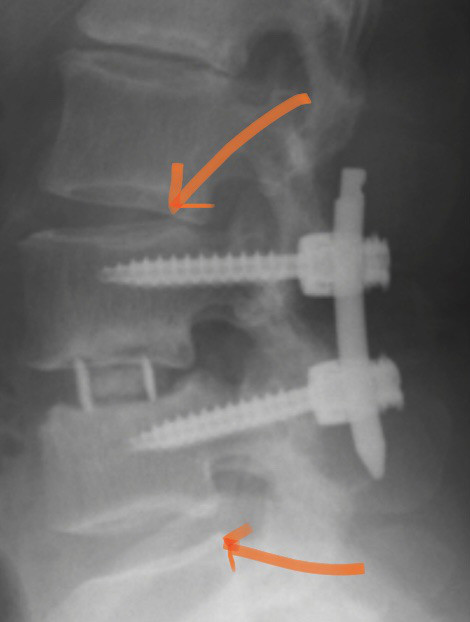

矢印のところが椎間板が痛んで炎症し痛みを引き起こしている場所です。

先日腰椎すべり症について書きましたが、すべり自体が根治することはないですが、症状を改善することができます。

すべり症とは腰椎が椎間板の変性などによって腰椎が前方に動いてしまうことで腰痛を引き起こしたり、脚に痛みやしびれ、筋力低下、感覚鈍麻などの神経症状が出ます。

4番目の腰椎がすべることが多く、腰を反ると腰痛を誘発します。立ち上がりの際、朝起きる時が痛いなどが患者さんの訴えとして多いのも特徴です。

症状が強いと手術することもあります。

腰椎を固定するためにインプラントを入れる手術をします。

しかし、手術をしても体幹機能の改善をしないとまた腰痛を引き起こすことがあります。

すべり症は治ることがなくても手術をせずに改善することがあります。

神経症状が出ていても神経の通り道を確保し、体幹機能の改善、腰椎屈曲のストレッチをすると症状を改善することができます。

私は腰椎専門の整形外科で働いていてすべり症の患者さんを多くみていますが、手術をするとインプラントが入る分手術した腰椎の上下が負担になって新な腰痛、神経症状が出ることがありますのでできるだけ自分の努力で改善することが望ましいと思います。